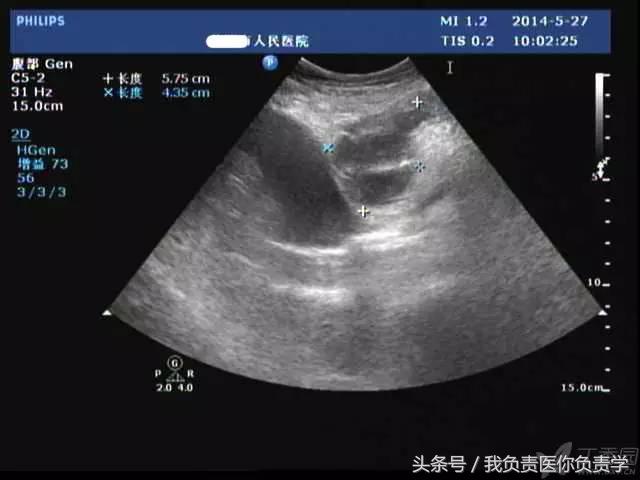

典型病例 1

患者男,64岁,因右上腹疼痛半月余就诊。查体发现右上腹部轻压痛,无发热。超声检查所见如下:

图1示胆囊增大,囊壁增厚,囊内透声差